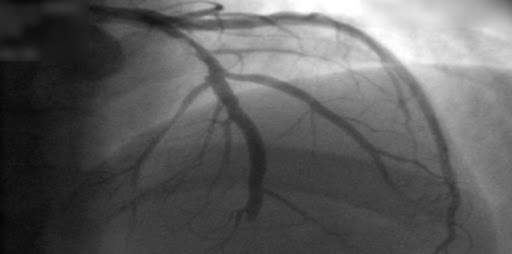

En esta declaración científica, revisamos la ciencia contemporánea, las consideraciones clínicas y los desafíos futuros para las puntuaciones de riesgo poligénico de enfermedades cardiovasculares. Seleccionamos 5 enfermedades cardiometabólicas (enfermedad de las arterias coronarias, hipercolesterolemia, diabetes tipo 2, fibrilación auricular y enfermedad tromboembólica venosa) y la respuesta a la terapia con medicamentos y ofrecemos orientación provisional a profesionales de la salud, investigadores, legisladores y pacientes. Circulation, 18 de julio de 2022